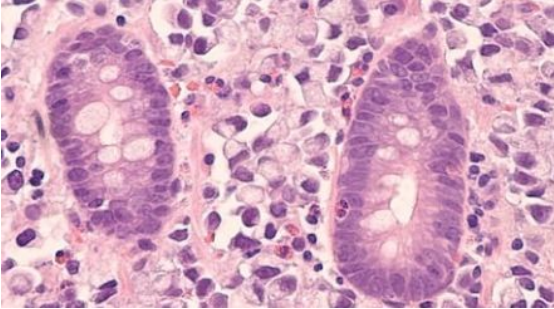

干細(xì)胞歸巢是指內(nèi)源或外源性干細(xì)胞在多種因素的作用下,能定向趨向性遷移,越過(guò)血管內(nèi)皮細(xì)胞至靶向組織并定植存活的過(guò)程,類(lèi)似人體局部炎癥反應(yīng)后大量白細(xì)胞遷移至炎癥周?chē)?/span>

干細(xì)胞周?chē)募?xì)胞形成像搖籃樣的環(huán)境保護(hù)著干細(xì)胞,這一環(huán)境被稱(chēng)為微環(huán)境(干細(xì)胞巢,niche)。niche 不僅給干細(xì)胞提供養(yǎng)分,同時(shí)還指導(dǎo)干細(xì)胞的行動(dòng),決定干細(xì)胞的分化方向。

微環(huán)境是由干細(xì)胞相鄰的各種細(xì)胞、細(xì)胞外基質(zhì)(extracellular matrix, ECM)以及多種細(xì)胞因子等構(gòu)成。